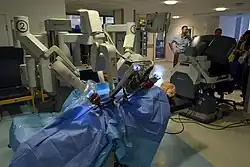

Roboterunterstützte Chirurgie

Chirurgische Roboter sind hochgenaue Industrieroboter, also mechanische Arme, die vom Computer gesteuert werden. Roboterunterstützung besteht immer aus dem Zusammenspiel des Chirurgen und des Roboters; selbsttätig operierende Roboter gibt es bisher nicht. Nach dem Grad der Interaktion unterscheidet man telechirurgische, shared-control-, und beaufsichtigte (supervised-controlled) Roboterchirurgie. Beaufsichtigte Eingriffe werden nach ausführlicher Vorbereitung vom Roboter ausgeführt, welcher vorprogrammierte Befehle umsetzt; der Chirurg beobachtet es und kann jederzeit unterbrechen. Bei shared control ("gemeinsame Steuerung") führt der Chirurg das Instrument, während der Roboter es aktiv stabilisiert (z. B. Zittern verhindert oder es von vordefinierten Positionen fernhält). Bei der Telechirurgie steuert der Chirurg die Roboterarme selbst. Seine Konsole kann dabei direkt neben dem Patienten stehen oder beliebig weit entfernt; selbst auf einem anderen Kontinent.

Das chirurgische System Da Vinci wurde von Intuitive Surgical, einem Zweig des Stanford Forschungsinstituts (USA), entwickelt. Da Vinci ist ein telechirurgisches System, meist verwendet bei laparoskopischen Bauch-OPs. Im Jahr 1997 hatte es die Zulassung von der FDA erhalten und war 2000 der erste Remote Manipulator, der die FDA-Zulassung bekam, Stand-alone-Operation durchzuführen. Nach heftigen Auseinandersetzungen fusionierten schließlich die beiden Hersteller, noch unter der Marke von Intuitive Surgical.